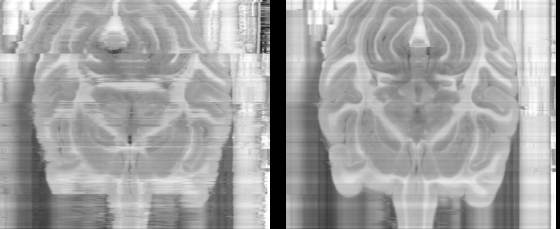

Figure 1: One of over 1000 cross-sections through 1182 slices of a brain; unregistered (left), registered (right)

The Three-dimensional Polarized Light Imaging (3D-PLI) technology is used to capture high resolution images of thinly sliced sections of post-mortem brains. These images can then be stacked to reconstruct the brain in three dimensions.